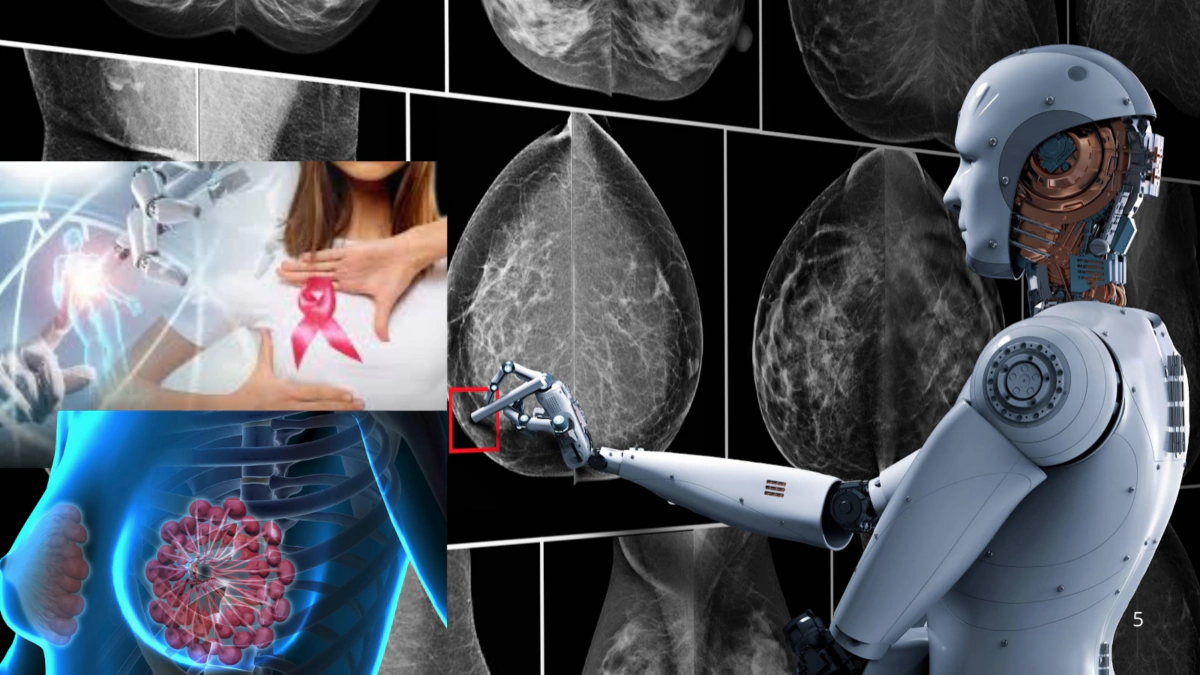

Inteligencia artificial mejora detección temprana del cáncer de mama

Un estudio en Suecia muestra que el uso de IA en mamografías detecta más casos tempranos, aunque los expertos recalcan su uso como apoyo al criterio médico para prevenir la dependencia excesiva.

La inteligencia artificial podría transformar la forma en que se detecta el cáncer de mama durante los chequeos rutinarios. Un ensayo clínico sugiere que esta tecnología ayuda a identificar señales difíciles de ver en las mamografías y reduce los casos que se diagnostican entre revisiones médicas, conocidos como “cánceres de intervalo”, que suelen ser más agresivos.

Un estudio realizado en Suecia, con más de 100,000 participantes, encontró que las mamografías asistidas por inteligencia artificial detectaron más casos de cáncer en etapas tempranas y redujeron la aparición de tumores diagnosticados entre evaluaciones. Los resultados fueron publicados el 29 de enero en la revista médica The Lancet.